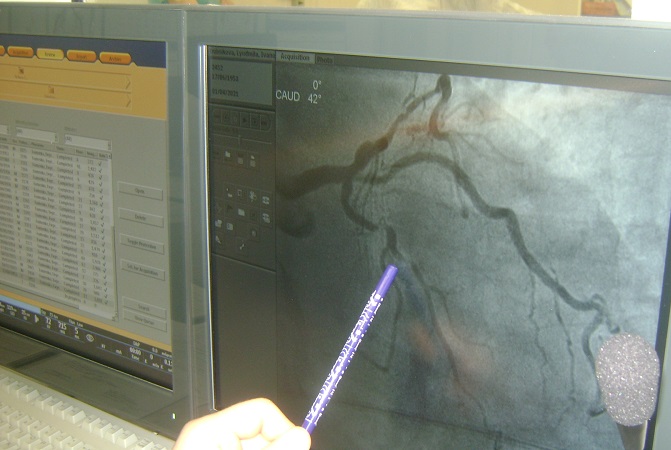

«Больной — возрастной, 82 года. Привезли по «скорой помощи» в 19 часов. Диагноз – острый инфаркт миокарда с подъемом сегмента ST. На снимке видна крупная огибающая артерия, полностью закрытая тромбом. Очевидно, что речь идёт об обширном участке поражения сердца», — рассказывает подробности состояния своего пациента хирург Евгений Фоменко. Спасать таких кардиобольных – это его работа и призвание.

«Обратите внимание, в правой коронарной артерии мы видим значимую атероскелотическую бляшку, которая суживает просвет сосуда. И так совпало, что эта артерия питает ту же зону, что и огибающая артерия. И обе они – в аварийном состоянии. Состояние больного критическое. Что делаем мы? Открываем! Используем специальный инструмент, диаметром меньше одного миллиметра. Это коронарный проводник, по которому в дальнейшем ходит весь остальной инструмент. Вводим его в сосуд. Видим, что бляшка и образовавшийся на ней тромб практически перекрывают просвет сосуда. Это можно сравнить с песочными часами. Резкое сужение диаметра до практически волоска», — рассказывает Евгений Петрович и водит ручкой по экрану компьютера. Мы смотрим запись одной из последних операций.